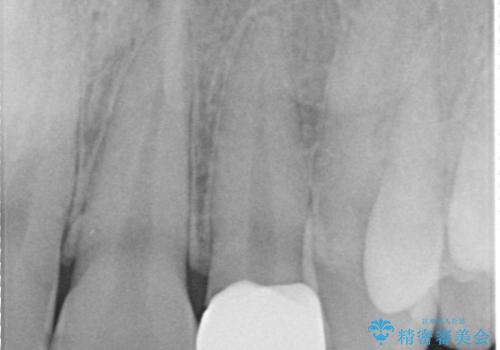

左上2番の大部分がプラスチックの材料で治療されていました。そのプラスチックの材料が劣化して変色し虫歯になっている状態でした。なので古いプラスチックの材料を全て除去し、その下の虫歯を取った後、オールセラミッククラウンで治療を行いました。オールセラミッククラウンを装着する前に当院にてホワイトニングを行いました。